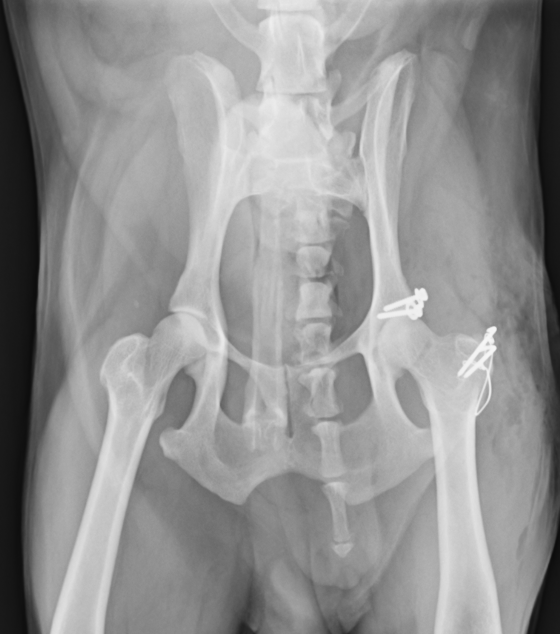

まずはワッシャーによる固定をご紹介します。大腿骨の大転子という部分を一時的に切断してから、骨盤臼にアプローチしてワッシャーを1つか2つ打ち込み、そこと大腿骨頭の骨頚部と呼ばれる部分に穴を開けてワイヤーを通し骨盤と大腿骨を固定する方法です。2週間ほど脱臼せずに維持できればその後は安定化していきます。

尾腹側脱臼では上記のワッシャーの方法は使用できず、トグルピン法か創外固定法、大腿骨頭切除の方法を用います。トグルピン方は、骨盤臼に穴を開け、そこにトグルピンと呼ばれる特殊な形のピンを挿入し、そこに引っ掛けた人工靭帯を、大腿骨に貫通させた穴に通して固定する方法です。この方法も2週間ほど維持できれば安定化していきます。